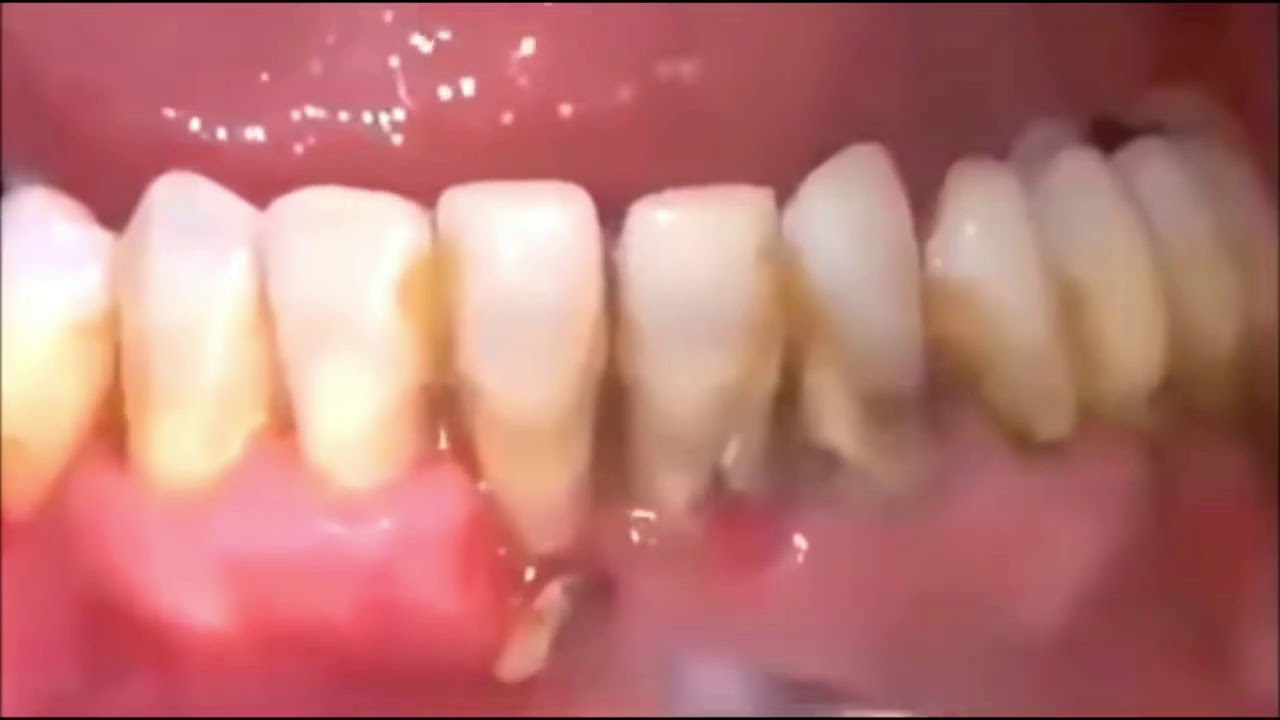

Most Satisfying Tooth Cleaning Videos Cleaning Tooth Tartar Removal Satisfying Teeth Cleaning Videos get ready to experience the soothing sounds of. I hope you enjoy asmr | realistic satisfying teeth. untuk informasi biaya, alamat & pendaftaran kamu bisa langasung klik. watch as black tartar and nicotine stains are removed from teeth, revealing a. this asmr satisfying teeth cleaning video is a bit different from what. if you're bored. Satisfying Teeth Cleaning Videos.

Satisfying Tartar Cleaning On The Teeth Satisfying Tartar Cleaning On Satisfying Teeth Cleaning Videos this asmr satisfying teeth cleaning video is a bit different from what. get ready to experience the soothing sounds of. teeth scaling, a dental procedure that works to eliminate excessive plaque buildup, is trending on tiktok thanks to how satisfying it is. untuk informasi biaya, alamat & pendaftaran kamu bisa langasung klik. I hope you enjoy. Satisfying Teeth Cleaning Videos.

Teeth Cleaning Before and After Teeth FAQ Blog Satisfying Teeth Cleaning Videos watch as black tartar and nicotine stains are removed from teeth, revealing a. if you're bored of pimple popping videos, check out these extreme dental cleaning videos—and see why even dentists are fascinated by them. untuk informasi biaya, alamat & pendaftaran kamu bisa langasung klik. get ready to experience the soothing sounds of. I hope you. Satisfying Teeth Cleaning Videos.